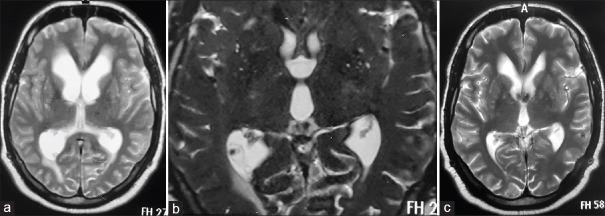

对2010年至2018年间接受内镜治疗的26例IVNCC患者的临床记录和随访进行回顾性分析。IVNCC的诊断基于脑部增强磁共振成像。通过额部钻孔进行0°内镜经颅内镜检查。进行第三脑室造瘘术并用血管导管切除囊尾蚴囊肿。

结果

第三脑室内囊肿的脑室内囊肿切除成功率,无论是完全切除还是部分切除,均为100%(14/14);第四脑室内囊肿为62.5%(5/8);侧脑室内囊肿为100%(4/4)。内镜下囊肿切除的总体成功率为88.46%。88.46%的病例成功建立了CSF流动通路。平均随访时间为44个月,所有患者在随访期间均无症状。